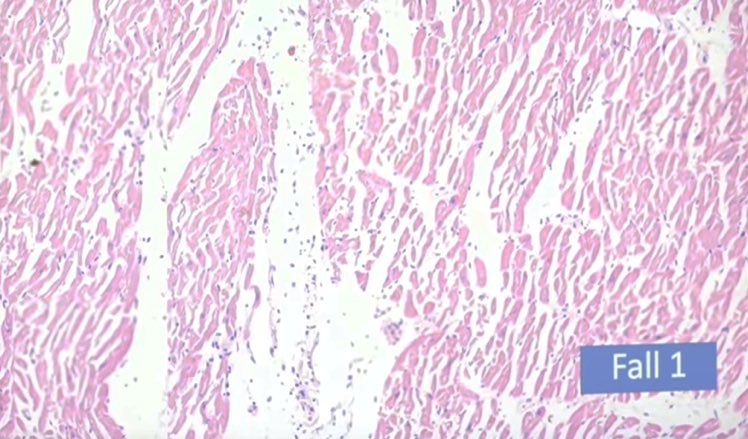

النتائج الرئيسية:

التهاب عضلة القلب اللمفاوي ، التهاب غشاء القلب ، التهاب التامور ، "غلبة الخلايا الليمفاوية" :

⁃نموذجي للعدوى الفيروسية

⁃يصعب التعرف عليها بالميكروسكوب ،

⁃غالبًا ما يُساء تفسيرها من الناحية النسيجية على أنها معدية (الخلايا الحبيبية!). 6️⃣

⁃عادةً ما تكون البؤر صغيرة متعددة ، وبالتالي لا يتم اكتشافها في كثير من الأحيان

⁃التأثير على قدرة الضخ (تحذير: وزن القلب الحرج)

⁃فشل القلب في الجهاز عندما يتأثر نظام التوصيل ؛ "الموت القلبي المفاجئ" ، الاكتشاف بالكاد ممكن (حوالي 15000 قسم)7️⃣